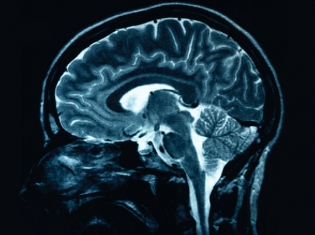

Miller had even tried electroconvulsive therapy (formerly known as electroshock) before trying a relatively new treatment called transcranial magnetic stimulation (TMS). TMS sends short pulses of magnetic fields to the brain. Miller felt the positive results after a few weeks.

During the treatment, which lasts 35 to 40 minutes, the patient reclines in a comfortable chair while a magnetic coil placed next to the head sends short pulses of magnetic fields to the surface of the brain. This stimulates the brain cells and affect the mood-regulatory circuits deeper inside the brain.